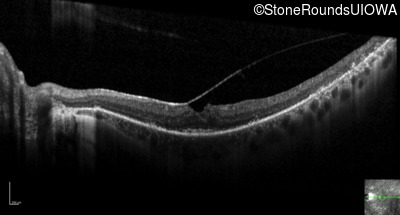

Optical Coherence Tomography - Right - 20/20

Exemplar / OCT Stack

OCT Stack